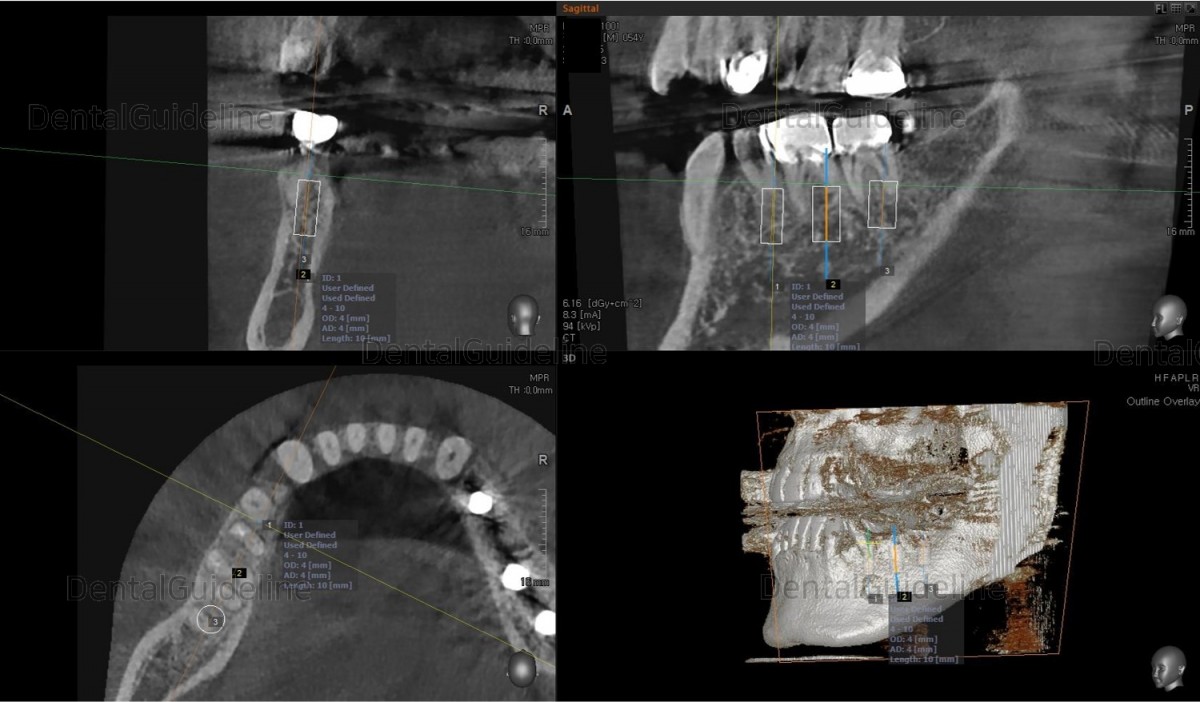

Surgery simulation to find the optimal

size, position, and direction of implants.

2nd premolar –Arum NB

Ø4.0L10 (30Ncm), 1st molar-Arum NB

Ø5.0L10 (40Ncm), 2nd molar-Arum NB

Ø5.0L10 (30Ncm),